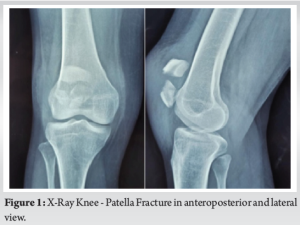

The patella serves as a pivotal component in the biomechanical function of the knee extensor apparatus [1]. Fractures of the patella have the potential to disrupt this mechanism, particularly when combined with incongruent posterior articular surfaces, leading to persistent issues like discomfort arising from femoropatellar arthritis [2,3]. Patellar fractures commonly stem from two primary mechanisms: Direct impact on the anterior knee or indirect injury resulting from eccentric contraction of the quadriceps muscle [4]. Surgical intervention becomes necessary in about one-third of patients affected by these fractures. Tension band wiring using stainless-steel wires has long been considered the gold standard for surgically managing displaced patellar fractures (Fig. 1 and 2) This technique effectively converts tension from muscle pull into compression at the fracture’s articular side, promoting improved fracture union by providing absolute stability through interfragmentary compression in bending fractures. However, its widespread use has been subject to debate due to the high incidence of resurgery rates attributed to issues such as implant impingement, skin infection, and wire breakage [5,6] (Fig. 3 and 4). Also for multifragmented stellate fracture, where encircle is required, SS wires require multiple passes through retinaculum with 4-mm-thick wire passer which is more traumatic. An alternative to traditional metal wire for patellar fracture fixation is non-absorbable suture, such as fiber tape (Fig. 5), which has been shown to yield similar outcomes with a reduced complication rate and comparable strength in biomechanical studies. Multiple passes in encirclage method for comminuted fractures with fiber tape is less traumatic with 2-mm needle. Research conducted by Arthrex found that fibreTape exhibited significant strength at 3 mm elongation and shows good loop integrity [7].

Introduction: Post-operative complications related to hardware, particularly symptoms caused by it, such as implant impingement, wire breakage, and skin infection are frequently reported following surgical management of patellar fractures with stainless steel wires. As a potential solution, some researchers have advocated for the use of non-absorbable sutures for fracture fixation. This study aims to investigate the clinical and radiological outcomes of patients treated with fiber taping as an alternative technique.